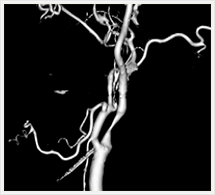

画像紹介

CTでは輪切り像の他にも立体的な画像(3D画像)を作成することもできます。そのためにはより細かくキレイな画像を撮影しなければなりません。当院では64列CTを導入しており、キレイな画像をより細かく撮影することができます。その画像を元に3D画像を作成することによって、より正確な手術のシミュレーションが可能になります。実際に手術をしたときの様子が、手術をする前に画像として見らます。外科系の手術には欠かせない技術となっておりますが、内科系でも血管内手術にも多く利用されております。

当診療放射線技術科では毎日各診療科に対して、その手術に最適な3D画像を提供しております。

以下にその3D画像を一部分紹介します。

頭部

頚部